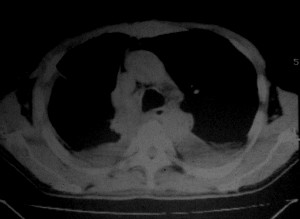

m ,60岁,右上肺ca术后一月。

纵隔淋巴结增大,双侧胸水。考虑术后残留,而非复发。

腹水,肝及右肾多发低密度影。考虑转移。

1、右肺癌术后改变。2、双侧胸水、腹水。3、多发性肝囊肿,右侧肾囊肿。

目前转移或复发的依据不足,术后才一个月,个人认为还是让临床去判断,而且需结合术前常规检查,有无肝肾囊肿;另外有一个疑问:肝胃间隙内团状软组织影是胃食管交接区吗,胃腔太小了吧,有无手术史请楼主告知.